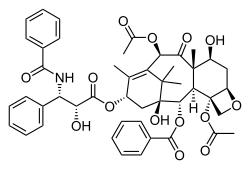

Достижения в этой области привели к внедрению некоторых методов лечения, нацеленных на дефекты сборки веретена. Старые методы лечения, такие как алкалоиды барвинка и таксаны, нацелены на микротрубочки, которые сопровождают образование митотического веретена, путем нарушения динамики микротрубочек, которые задействуют SAC, останавливая клетку и в конечном итоге приводя к её гибели[75]. Таксол и доцетаксел до сих пор используются для лечения рака молочной железы, рака яичников и других видов эпителиального рака. Однако эти методы лечения часто характеризуются высокой частотой побочных эффектов и лекарственной устойчивостью.

Другие цели в сети регулирующих органов, влияющих на SAC, также преследуются; большой интерес сместился в сторону белков киназы aurora[76]. Ген киназы Aurora A при амплификации действует как онкоген, подавляющий SAC, что приводит к аномальному инициированию анафазы и последующей анеуплоидии, а также к резистентности к TAXOL[77]. Интересно, что низкомолекулярный ингибитор Aurora A продемонстрировал противоопухолевый эффект в модели in vivo, что позволяет предположить, что он может стать хорошей целью для дальнейшей клинической разработки[78]. Ингибиторы Aurora B, которые также находятся в стадии клинической разработки, приводят к аномальному прикреплению кинетохор к микротрубочкам, а также отменяют контрольную точку митоза[76]. Сурвивин также является привлекательной молекулярной мишенью для клинической терапевтической разработки, поскольку он действует как основной узел во множестве путей, одним из которых является формирование веретена и контроль контрольных точек[79]. Даже дальнейшие подходы включали ингибирование митотических моторных белков, таких как KSP. Эти ингибиторы, которые недавно прошли клинические испытания, вызывают остановку митоза и, задействуя контрольную точку сборки веретена, индуцируют апоптоз[80][3].